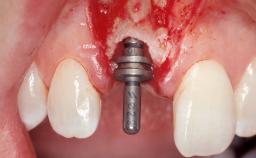

Late Placement of an Implant in a Maxillary Left Central Incisor Site

A 30-year-old female patient had lost tooth 21 and was referred to our clinic for consultation and treatment. Due to advanced apical infection, tooth 21 had been extracted two months earlier at another clinic and an acrylic-resin tooth had been bonded to the adjacent teeth. The patient desired implant treatment to avoid any damage to the adjacent natural teeth. While the patient had no history of any systemic disorder, she was a heavy smoker and exhibited medium to advanced periodontitis in the entire jaw. After the initial treatment to achieve a pocket probing depth of less than 4 mm and no bleeding on probing, a decrease in the height of the papillae mesial and distal to the extraction site and overall gingival recession were observed.

Type of Implants One-Piece|Reduced-Diameter

Bone Augmentation Horizontal|Staged

Augmentation Materials Autogenous chips|Membrane

Soft Tissue Grafting Simultaneous

Placement Protocol Early or late implant placement

Bone Volume Deficient horizontally, requiring prior grafting